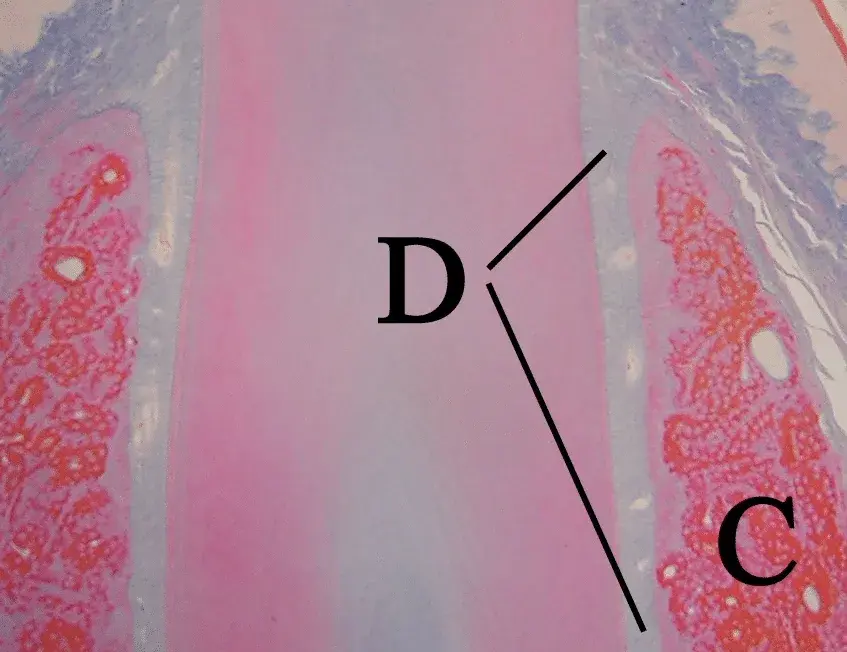

Perché il periostio è il fattore determinante nella sopravvivenza dell'osso dopo espansione crestale. Lo studio di Stricker et al. su COIR lo dimostra.

Bonebenders - Il potenziale osteogenico delle cellule derivate dal legamento parodontale (PDL) e dal tessuto di granulazione è confermato da numerosi studi

Il processo di osteointegrazione coinvolge una sequenza di adsorbimento delle proteine e migrazione cellulare nei primi minuti, che precede la deposizio...